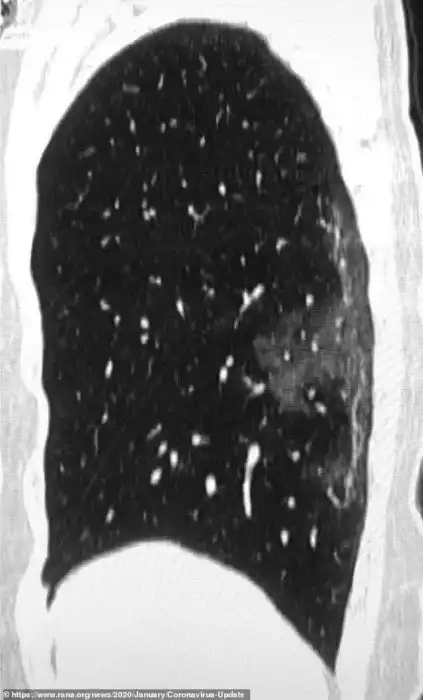

Рентгеновские снимки и томограммы легких 44-летнего пациента, умершего от коронавируса, были представлены китайскими врачами. Они дают подробную картину того, как вирус разрушает легкие человека. На снимках видны белые пятна в нижних отделах легких. Медики называют их "субплевральными уплотнениями по типу матового стекла". В этих областях воздушные пузырьки легких частично заполнены содержимым. Похожие поражения наблюдались также у пациентов с атипичной пневмонией и ближневосточным респираторным синдромом.

Это - снимок легких 45-летней женщины из Сычуани, протестированной после возвращения из Японии и диагностированной как носительница вируса. На снимке видно некоторое количество аналогичных образований, но здесь они сосредоточены в верхней доле левого легкого.